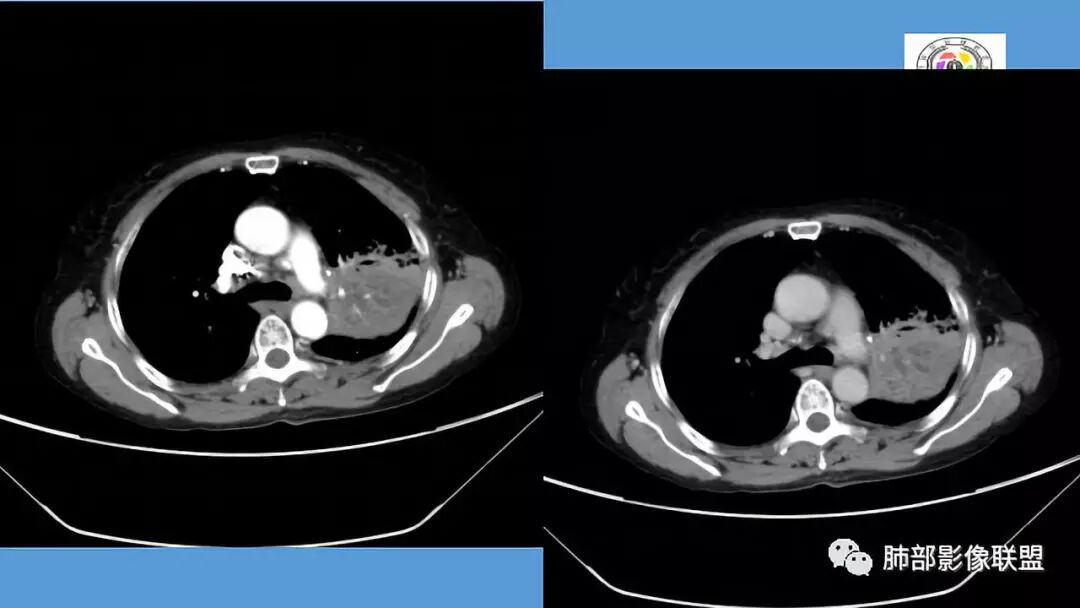

1.双肺多发病灶,结节影、树丫影,边缘分布……病灶符合继发性肺结核。

2.左肺上叶大片实变影,密度不均,体积轻度增大,注意轻到中度强化及血管影未见破坏、未见坏死空洞……病灶更符合炎症,而不大支持干酪性结核及肺鳞癌等,后两者的破坏能力是比较强的。

3.支气管阻塞,沿途可见钙化及液性潴留……更符合支气管内膜结核。

综上,双肺继发性肺结核诊断应当成立;左肺上叶大片影,以支气管内膜结核伴阻塞性炎症解释更为合理。